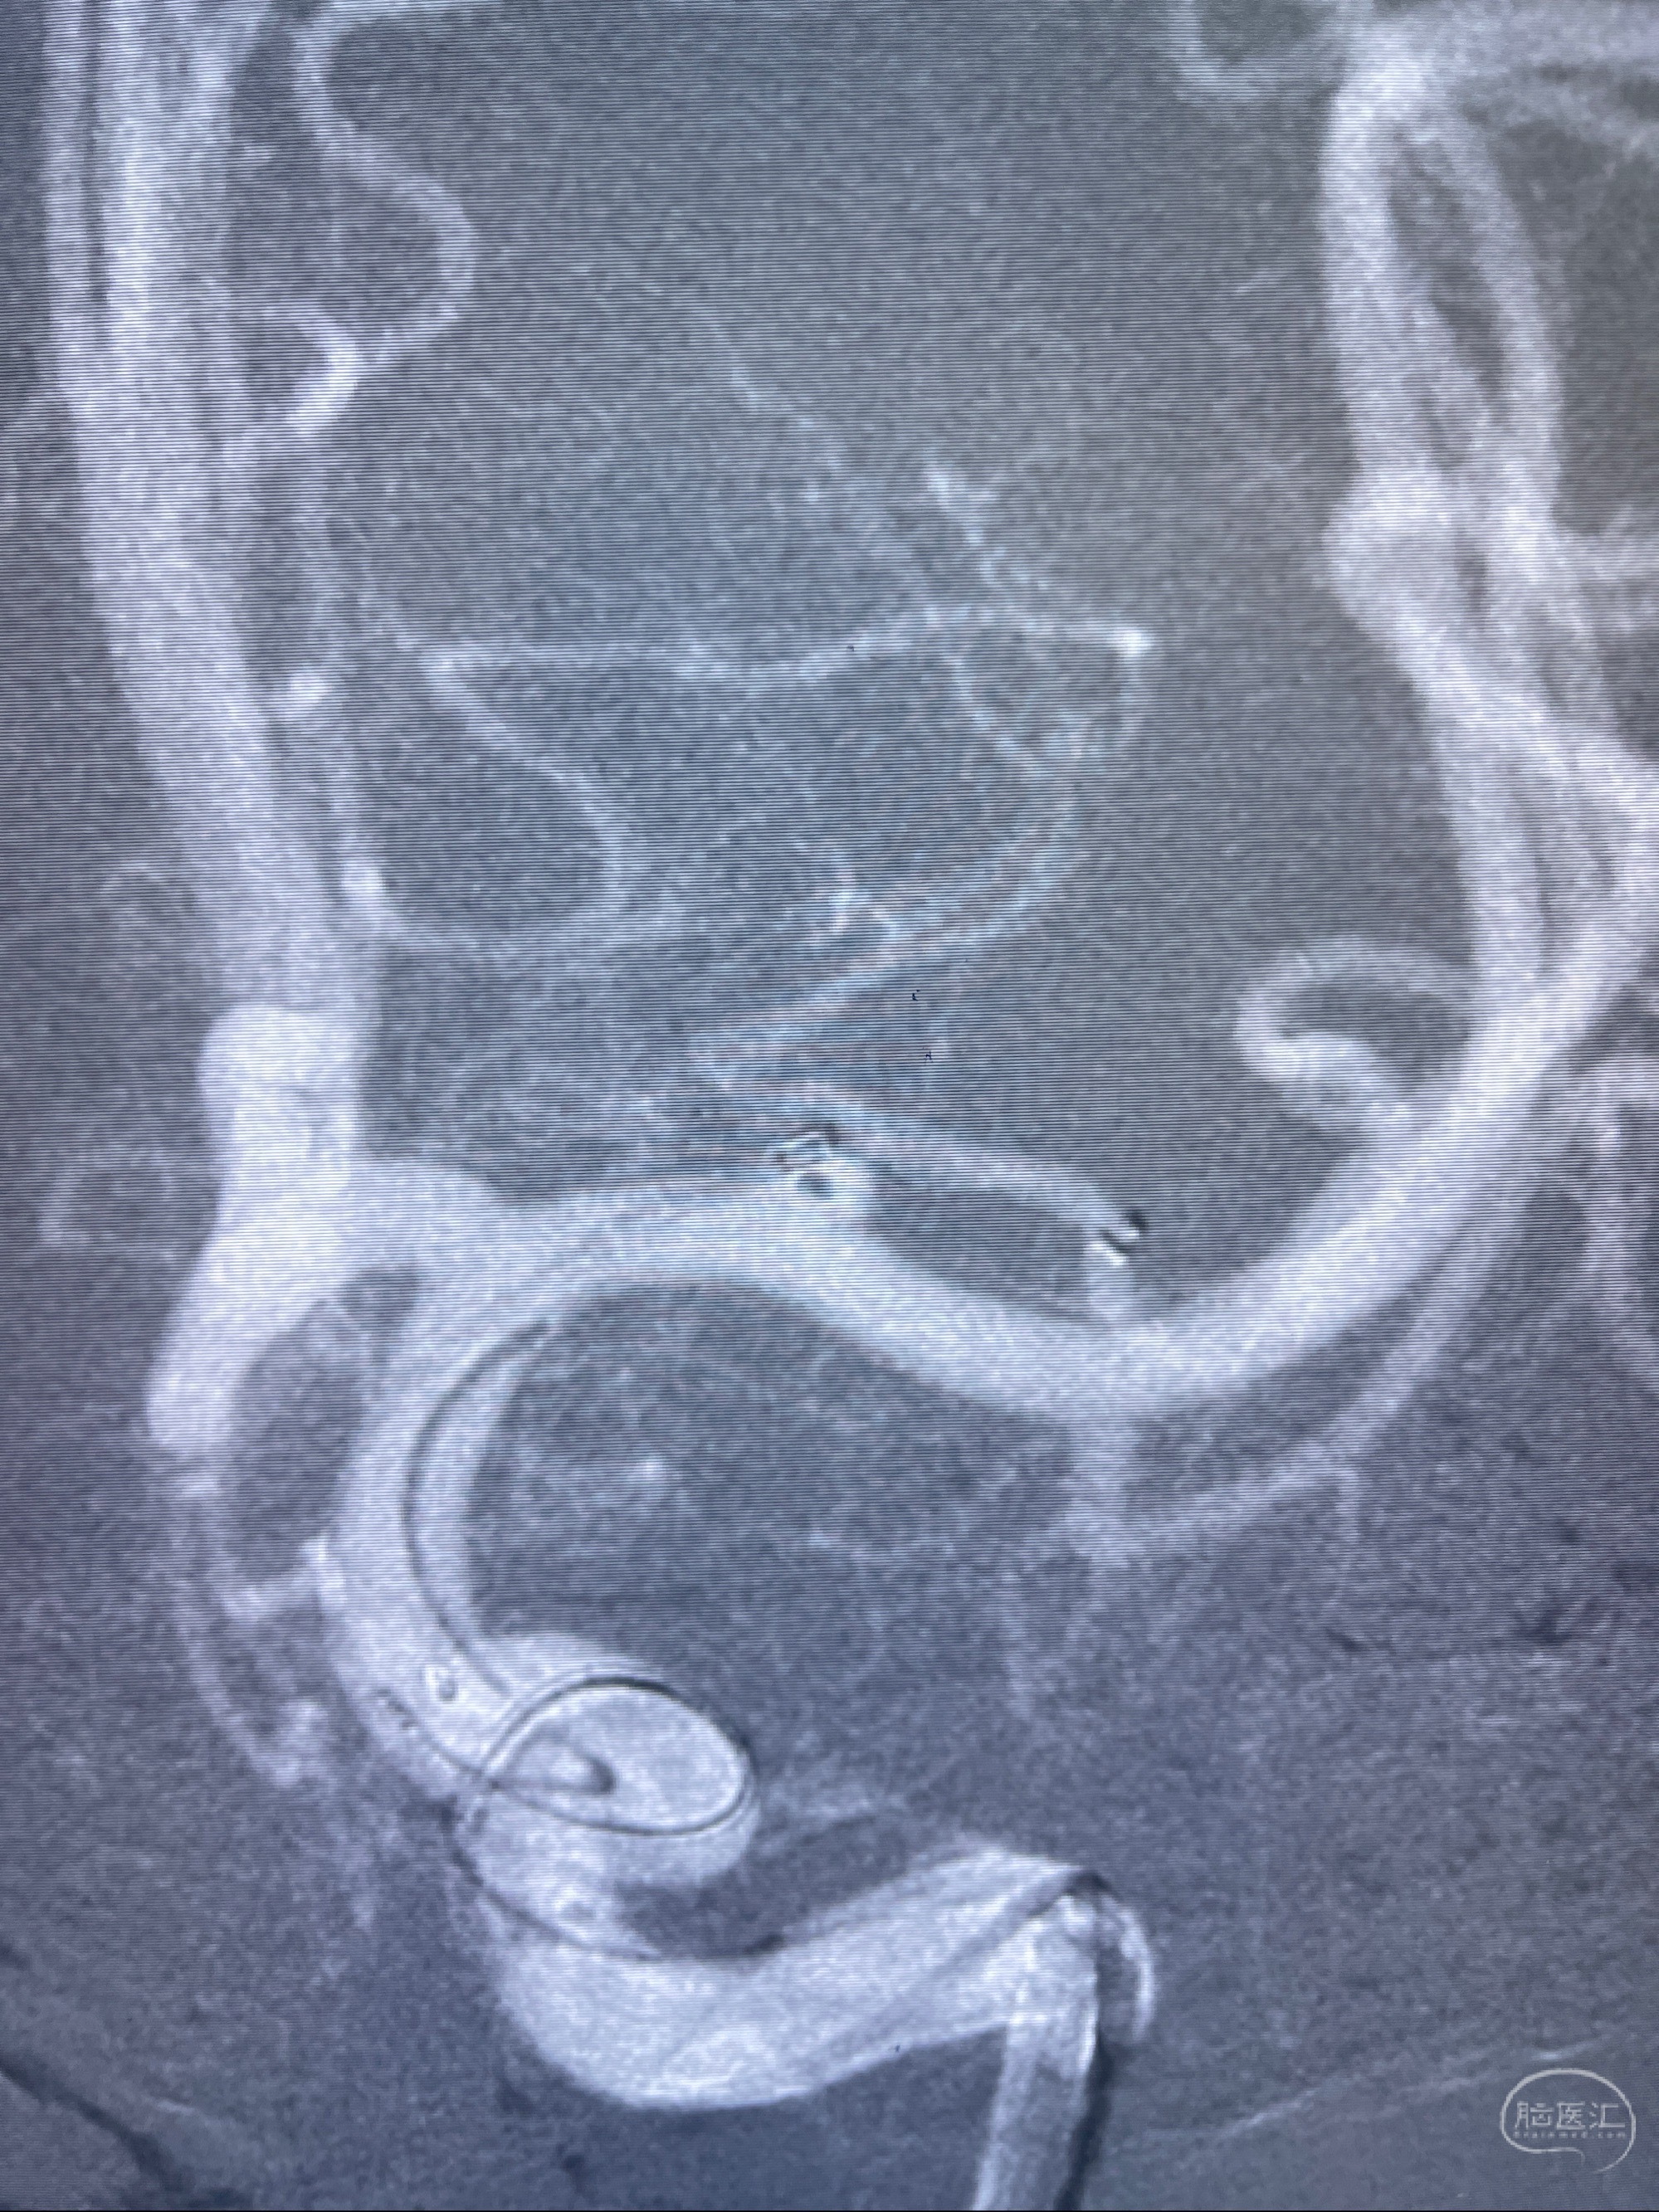

2023-08-14DSA:

左侧大脑中动脉动脉瘤,约2.6-2.8-3.4-2mm大小(瘤颈部、瘤体部、瘤高)